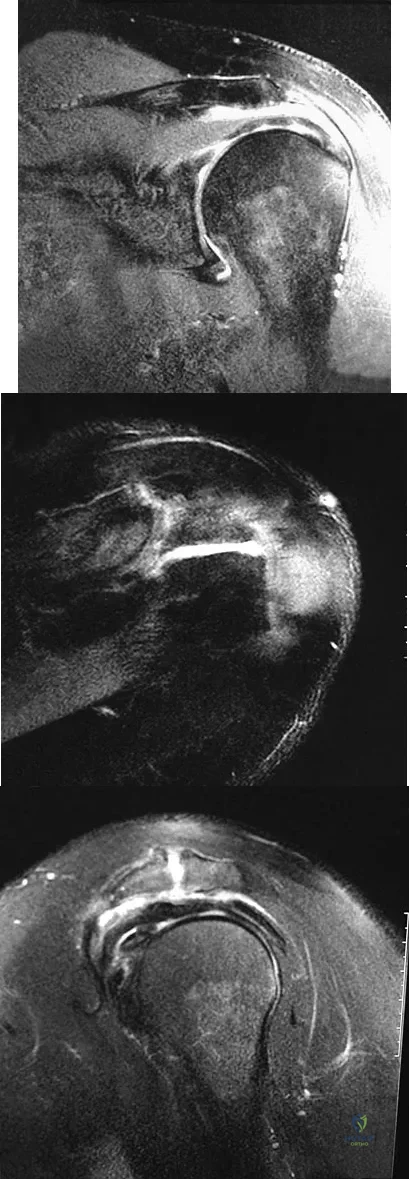

Figures 26a through 26c show the MRI scans of a 47-year-old man who underwent arthroscopic shoulder surgery 6 months ago and continues to have pain despite a prolonged course of rehabilitation. Management should now consist of

Explanation